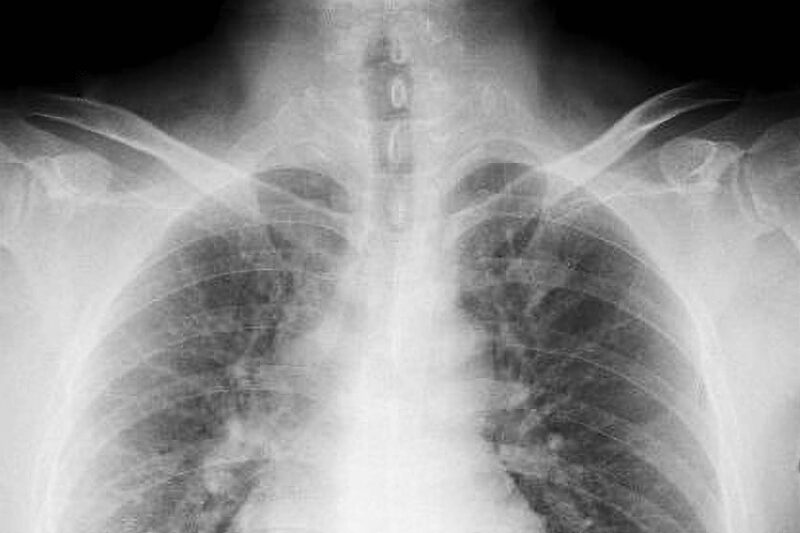

- 영상 검사 : 흉부 X선, CT 스캔 등을 통해 염증의 정도나 기타 이상을 평가합니다.